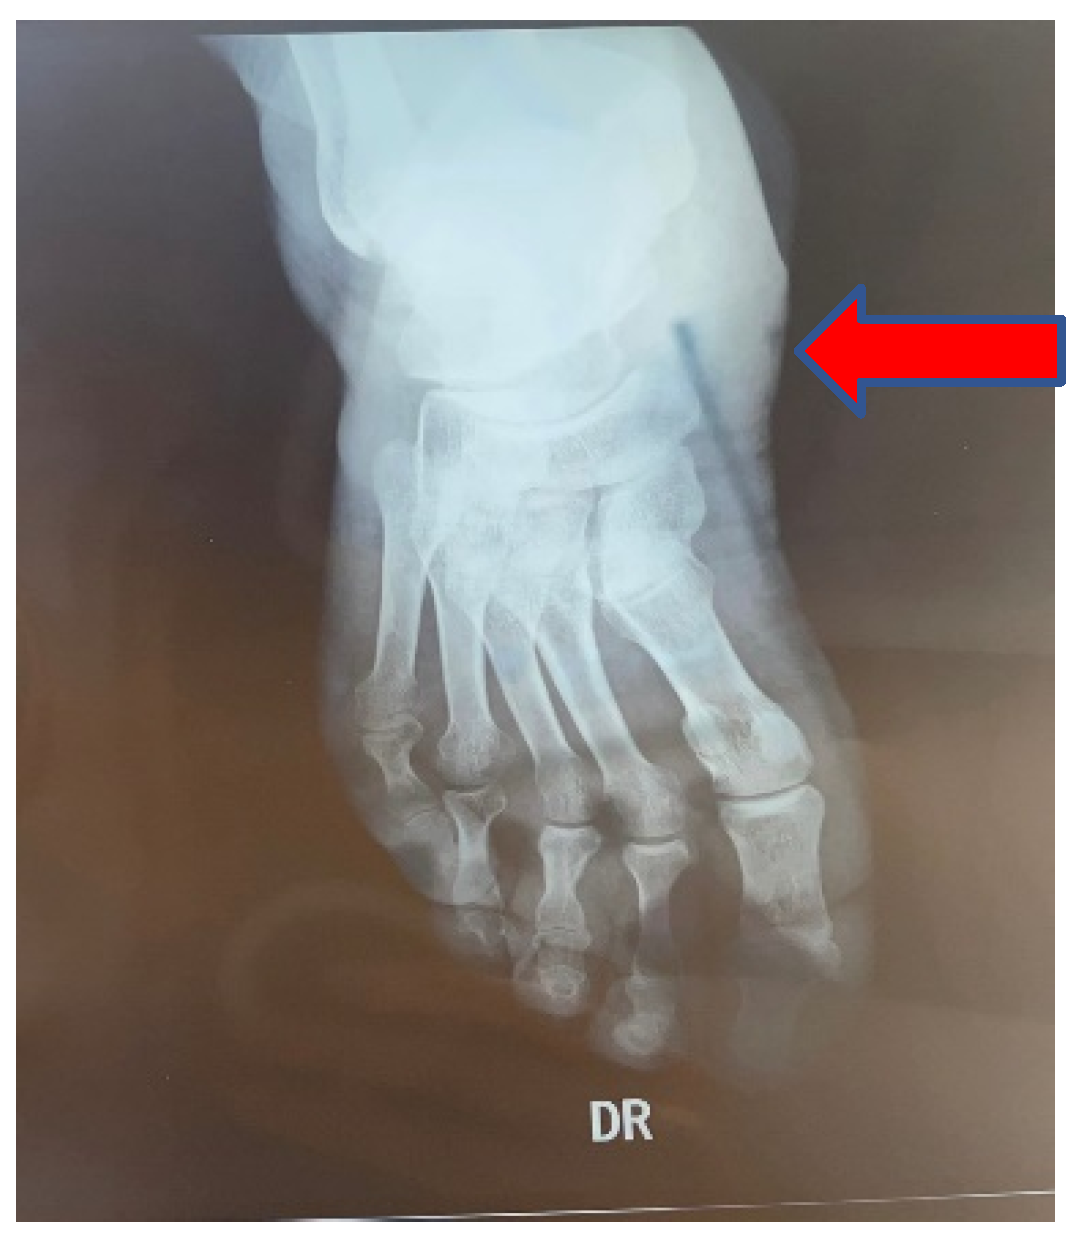

1.7. Clinical Features and Classifications